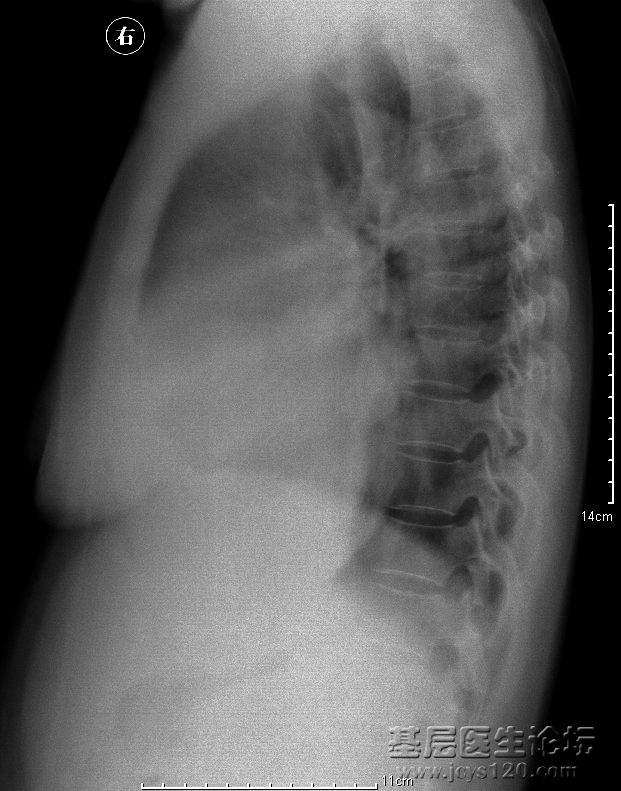

• 患者男,85岁,咳嗽咳痰,吸烟,余病史未知。 胸部正位 侧位 诊断报告:   两侧胸廓对称,气管上纵隔居中,右侧肺动脉干增粗,双肺纹理增粗紊乱以左肺较为明显,可见大量点片状低密度影呈蜂窝状。主动脉弓迂 ...  阅读全文>